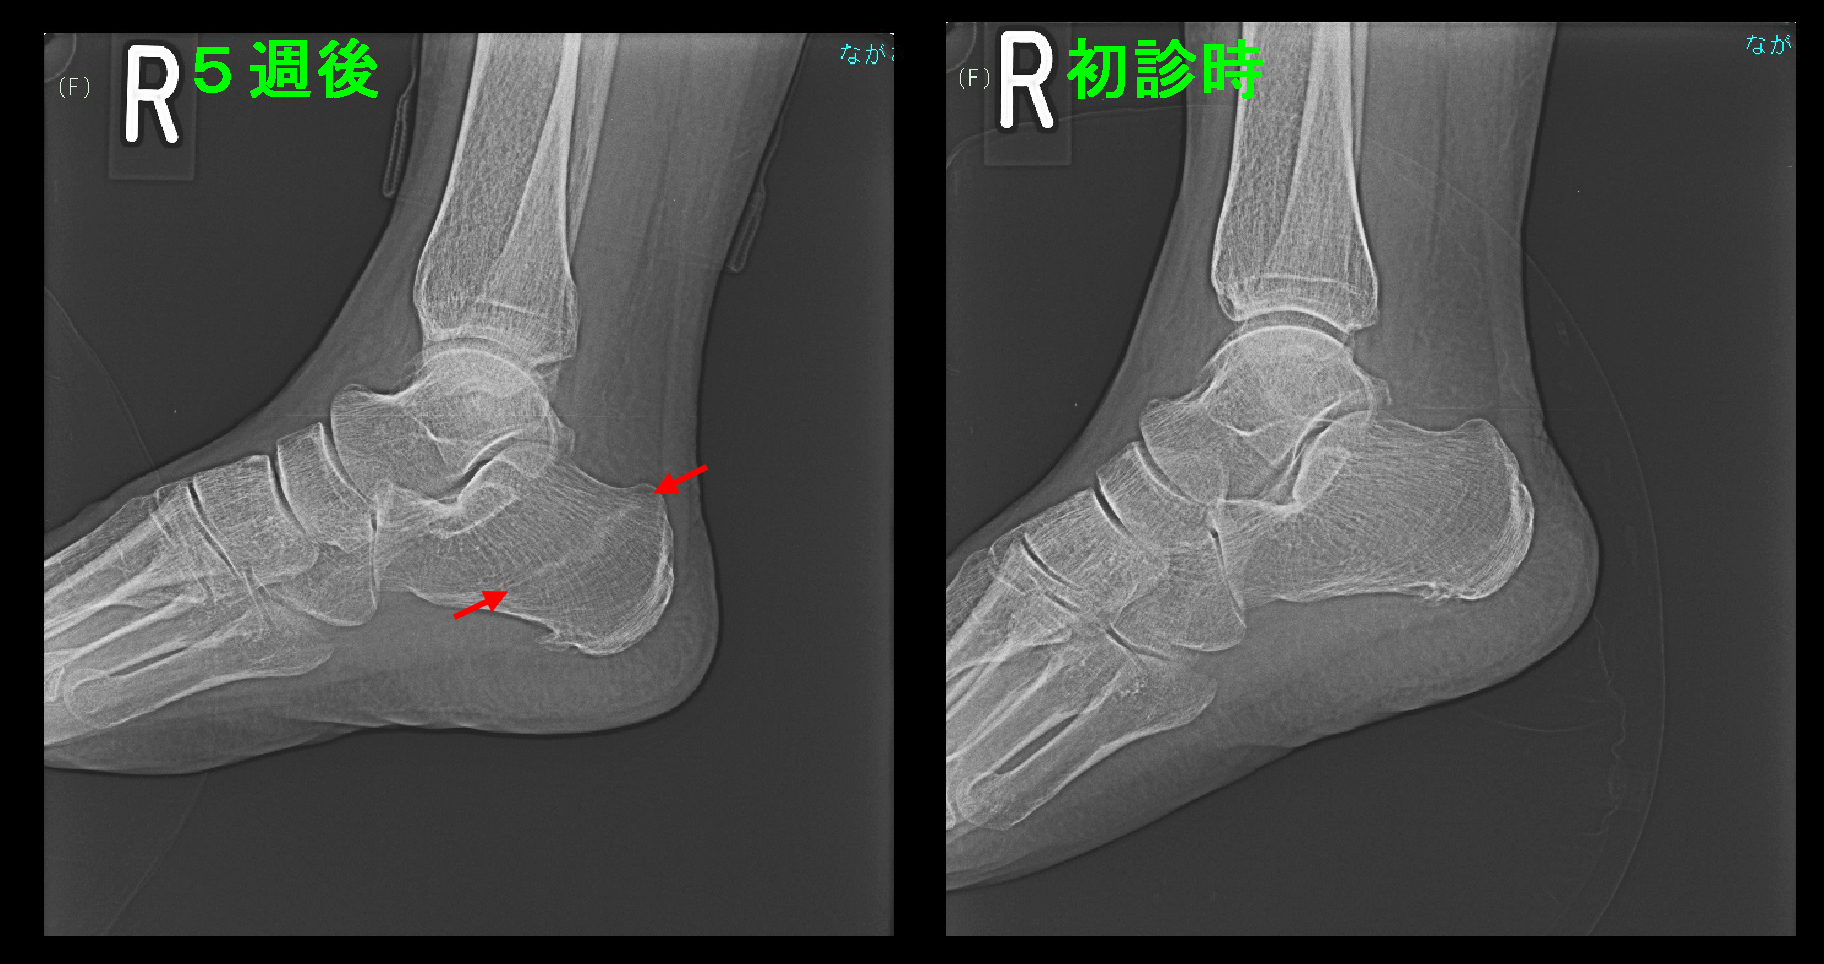

初診時Xp.jpg

MRI検査を行うと、左側のSTIRの条件で黒い踵の骨(踵骨=しょうこつ)が白くなり、疲労骨折の状態でした。右側のT1という条件では内側の骨の壁が黒くなり、ひびと診断されました。

5週後Xp.jpg

5週後のレントゲン像では踵骨内の疲労骨折部に仮骨(=新生骨)ができていることが分かります。